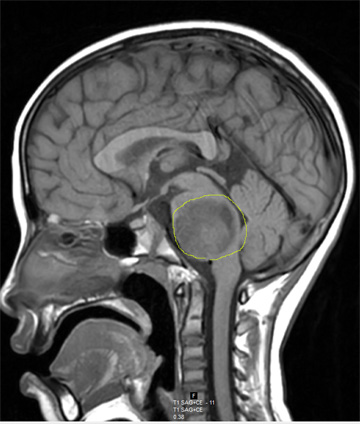

그런데 지난 9월 중순 갑작스런 어지러움증 때문에 방문을 잡고 쓰러졌고 이후 현지 병원 MRI 검사를 통해 뇌간에 4.5cm 크기의 종양이 자라고 있음을 발견하게 되었습니다. 발병 부위가 생명현상을 관할하는 부위라 수술도 힘들고 하루가 다르게 힘이 빠지고 말도 어눌해지고 있습니다.

한 달전부터 온 교회가 쟌사야를 위해 기도하고 있고 이곳을 방문했던 단기팀까지도 잔사야를 위해 기도 중입니다. 그러나 우리의 바램과 달리 쟌사야는 날이 갈수록 점점 더 힘이 빠지고 팔도 굳어져 갑니다. 의식이 희미해져가는 쟌사야를 바라보는 우리의 맘은 안타까움으로 타들어갈 뿐입니다. 쟌사야가 가진 병의 치유를 위해, 이 일로 쟌사야의 가족의 믿음이 더욱 굳세어지도록 기도해주세요.